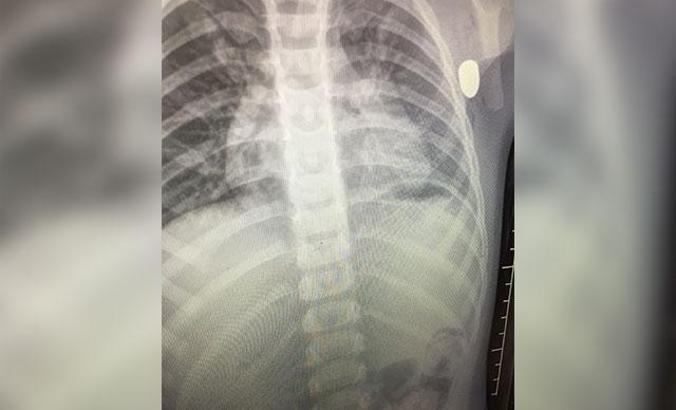

Durumu ağırlaşan Aydemir, sevk edildiği kent merkezindeki Eğitim ve Araştırma Hastanesi'nde ameliyata alındığı öğrenildi. Tedavisi süren Aydemir'in maganda kurşununun hedefi olduğu, yorgun merminin de sol kolunun alt kısmından girip, göğsüne saplandığı tespit edildi. Soruşturma başlatan polis, silahı ateşleyen kişinin tespit edilmesi için çalışma başlattı.